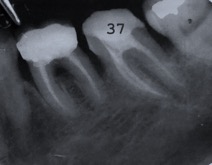

Capita spesso di incontrare denti già devitalizzati in maniera impropria che necessitano, seppur asintomatici, di essere ritrattati per evitare che i granulomi infetti visibili radiograficamente si evolvano riassorbendo tutto l’osso sottostante.

Un adeguata endondonzia serve per salvare quei denti che altrimenti sarebbero destinati ad essere estratti. Quando un dente viene devitalizzato viene privato della sua irrorazione sanguigna e del nutrimento, rendendo la sua struttura più “vetrosa” quindi più fragile e soggetta a fratture. Per questo motivo è consigliabile nella maggior parte dei casi capsulare i denti una volta che hanno perso la loro vitalità.